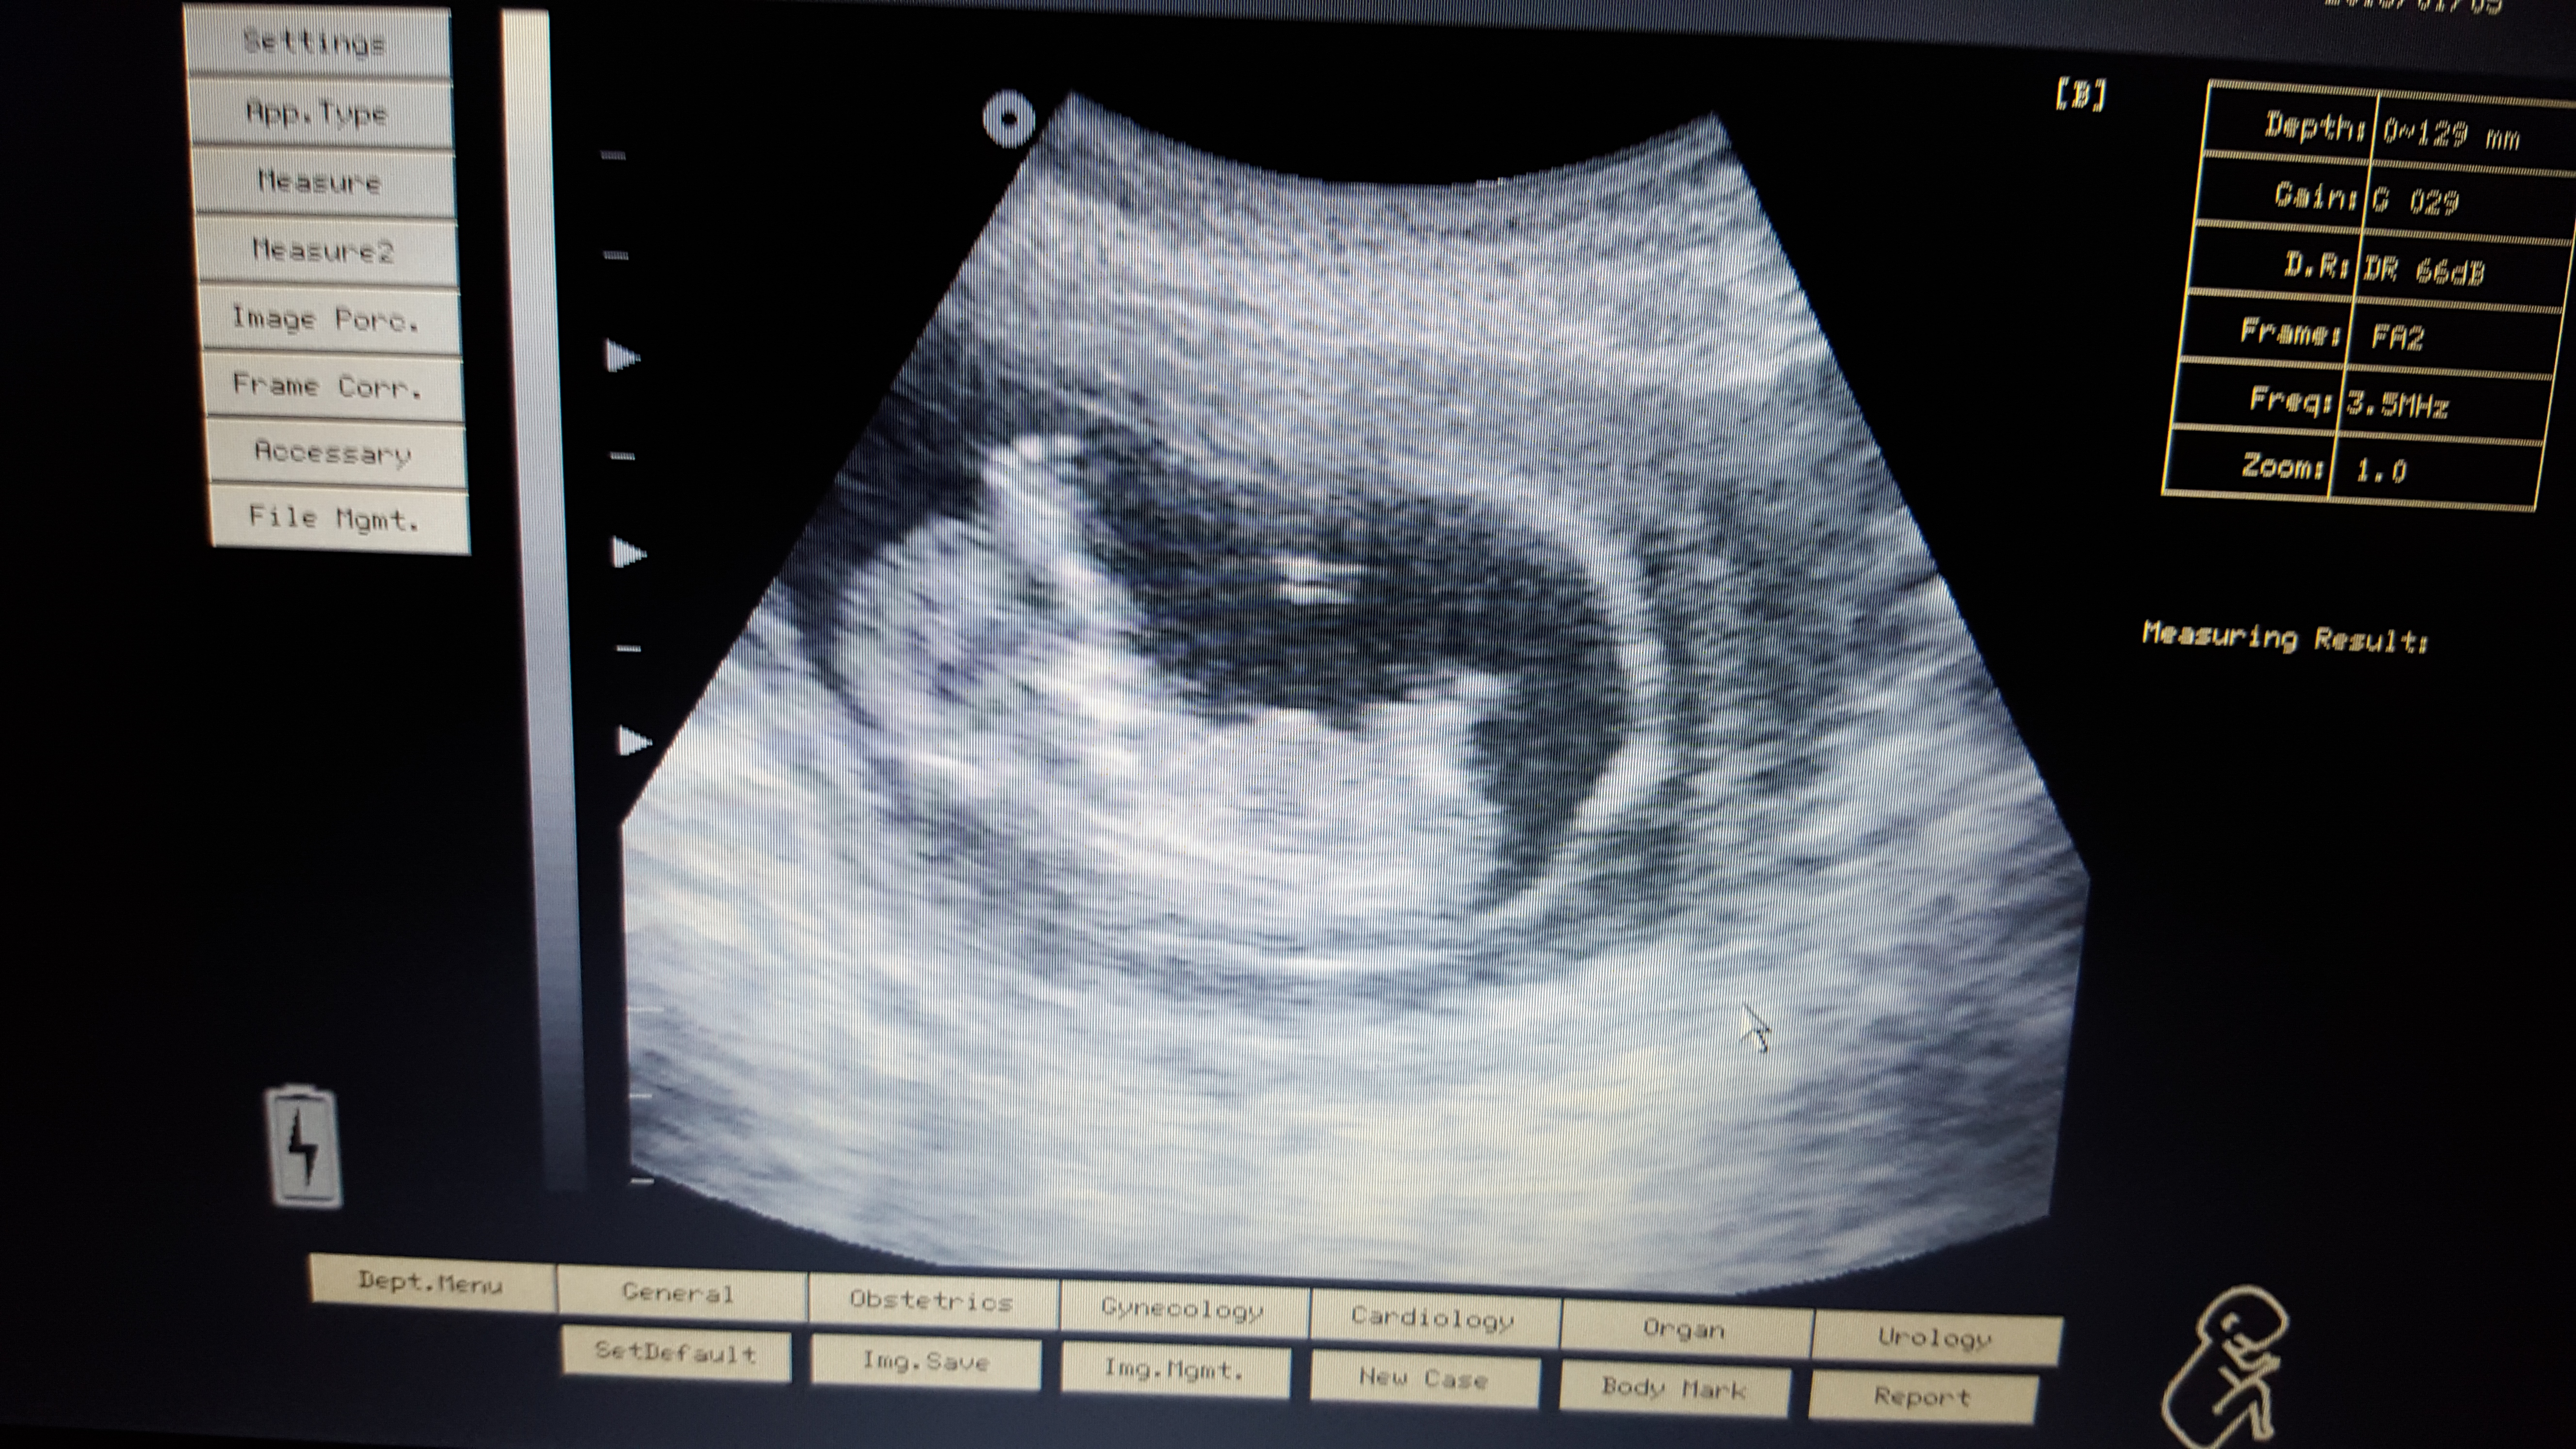

Pink or blue? These are taken at 13+3

Attachment 29187

Babies hands were around genital area alot so may of caught that in some of the photos!